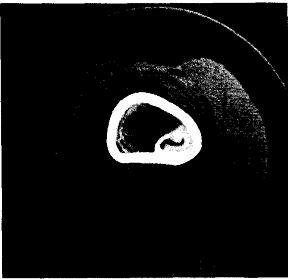

Злокачественная остеобластома. Рядом авторов были описаны случаи озлокачествления остеобластом после одной или нескольких нерадикальных операций; по времени этот процесс растягивался на 5—9 лет [Mayer L., 1967, 1968; Schajowicz F., Lemos D., 1970; Lichtenstein L., 1972; Dorfman H.D., 1973; Scrauton P.E. et al., 1975; Seki T. et al., 1975; Jackson R., Bell E.T., 1977; Merryweather R. et al., 1980, и др.]. Иногда рецидивы принимались за остеобластический вариант остеогенной саркомы, однако клиническое течение у всех больных было мягче. Только у 3 пациентов наблюдались легочные метастазы [Lichtenstein L., 1972; Sebi et al., 1975; Merryweather R. etal., 1980]. Первично-злокачественную остеобластому — клинику, рентгенологическую, морфологическую картину — описали в 1976 г. F. Schajowicz и D.Lemos, под наблюдением которых находились 8 подобных больных (в дальнейшем они наблюдали еще 2 больных). По их мнению, провести дифференциальный диагноз даже по гистологической картине между злокачественной остеобластомой и остеогенной саркомой трудно. Не являясь морфологом, я отсылаю желающих ознакомиться к их работам. Другие авторы называют эту форму агрессивной формой остеобластомы, продуцирующей остеоид с большим или меньшим количеством атипичных остеобластов. Рис. 20.2. КТ бедренной кости в костномозговом канале. Хорошо видны ободок склероза, прилежащий к кортикальному слою, и ядрышко.

Рис. 20.2. КТ бедренной кости в костномозговом канале. Хорошо видны ободок склероза, прилежащий к кортикальному слою, и ядрышко.